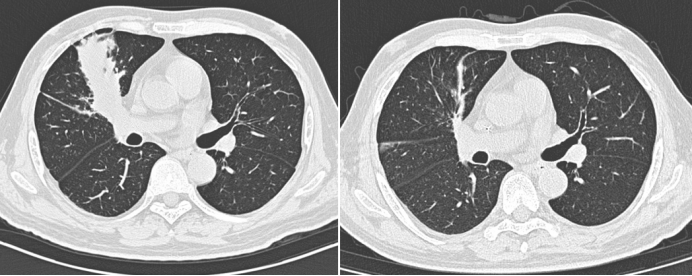

病例7男性,52岁。主诉:反复发热2个月。体温最高39℃。外院行胸部CT考虑“肺部感染”,多次查真菌G试验/GM试验均阴性,结核T细胞检测阴性。患者于外院共3次行电子气管镜检查。BALF-mNGS显示为轻链球菌、咽峡炎链球菌、人类疱疹病毒5型。反复抗感染治疗无效。既往史:2021年2月确诊为急性髓系白血病,行化疗4次,2021年4月11日行非血缘脐带血干细胞移植治疗。3个月前有可疑结核接触史。吸烟30余年,约20支/日。2021年6月17日胸部CT示右肺上叶前段、中叶、后叶均可见病变(图10)。组织病理学检查发现大量真菌菌丝及孢子(图11)PAS及GMS染色均呈阳性,结合上述结果可以明确诊断为毛霉感染,后续mNGS进一步印证了该诊断。支气管镜下2次冷冻活检取脓栓(图12)。予右肺上叶前段支气管共灌注两性霉素B 5次,每次15 mg。右肺下叶内基底段共灌注两性霉素B 5次,每次10 mg。经过4周的治疗,患者肺部病变消失(图13)。半年后再次复查支气管镜,镜下表现正常(图14)

图片

图10  病例7治疗前胸部CT

图13  病例7治疗前后胸部CT对比